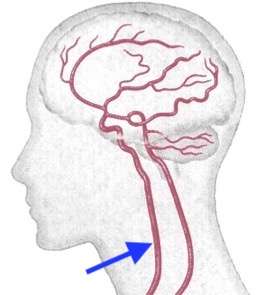

血管を冷やしてやれば、血管が収縮して痛みが軽くなります。しかし、脳の血管(動脈)は厚い頭蓋骨の中にあり、痛い場所を冷やしても血管まで届きにくいのです。脳の血管の入り口は総頚動脈と椎骨動脈です。主な脳血流は総頚動脈から流れていくので、下図のような首の横を冷やすと効果的です。

総頚動脈はほぼ耳の下、顎の骨よりも下の位置です。この場所は骨がないので、直接脳へ行く血液を冷やす事ができます。

ここを指の先でやや強めに圧迫してみると、脈打っているのがお分かりかと思います。その脈打つ場所が総頚動脈です。保冷剤などで冷やすのが良いでしょう。マスクで頭痛が起きた場合などにも有効です。